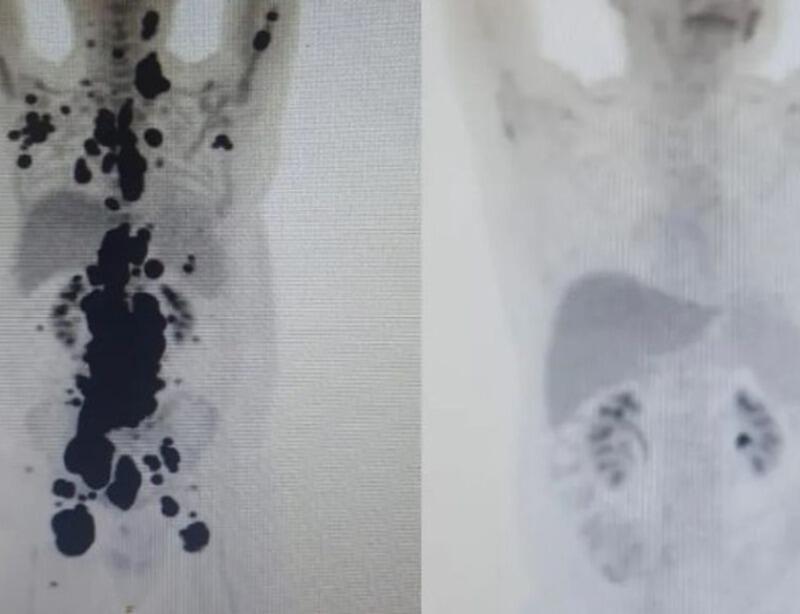

As duas imagens do Pet Scan (tomografia feita com um contraste especial) representam “dois Paulos”: a da esquerda, o paciente que tinha como caminho único os cuidados paliativos, quando a alternativa é dar conforto, mas já sem expectativa de cura, e a da direita, um paciente com um organismo já sem tumores após o tratamento com CAR-T Cell.

“Foi uma resposta muito rápida e com tanto tumor. Fico até emocionado [ao ver as duas ressonâncias de Paulo]. Fiquei muito surpreso de ver a resposta, porque a gente tem que esperar pelo menos um mês depois da infusão da célula. Quando a gente viu, todo mundo vibrou. Coloquei no grupo de professores titulares da USP e todo mundo impressionado de ver a resposta que ele teve”, comemorou o especialista.

“A vitória não é só minha. É da fé, da ciência e da energia positiva das pessoas. Cada uma delas ajudou a colocar um paralelepípedo nesse caminho. A imagem prova com muita clareza para qualquer pessoa a gravidade do meu linfoma, e eu não tinha ideia de que era assim”, contou o paciente.